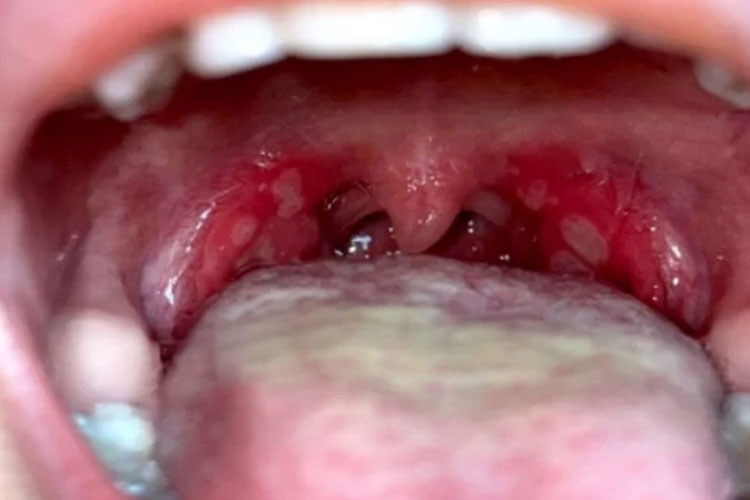

典型体征为咽部充血,口腔黏膜出现数个小的灰白色疱疹,周围绕以红晕。水疱期2-3天。

溃疡期红晕加剧并扩大,疱疹破溃形成黄色溃疡,儿童因溃疡疼痛出现流口水甚至拒食现象。